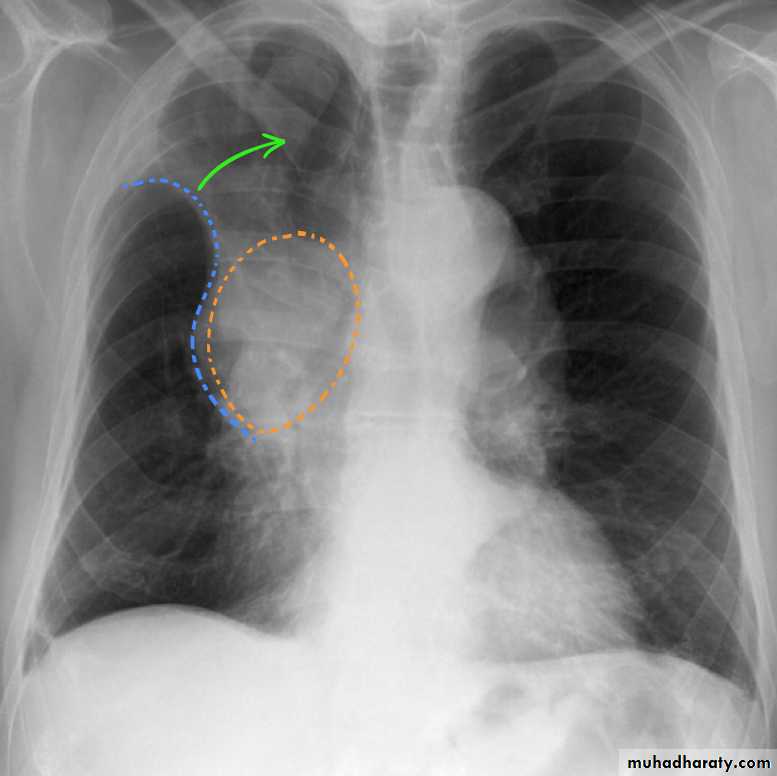

Mitral valve disease (double density RT cardiac border)

15.mitral valve disease & their sign

16.MVD